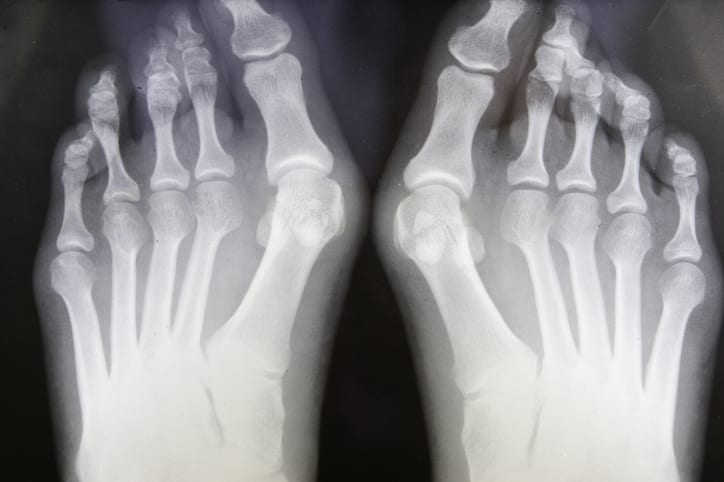

「外反母趾」理学療法士が教える〝足のアーチ〟を改善する簡単エクササイズ